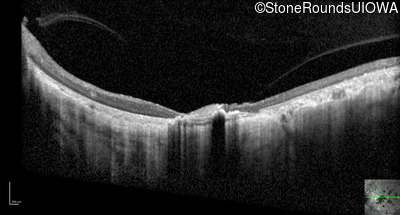

Optical Coherence Tomography - Right - 20/150 sc

Exemplar / OCT Stack